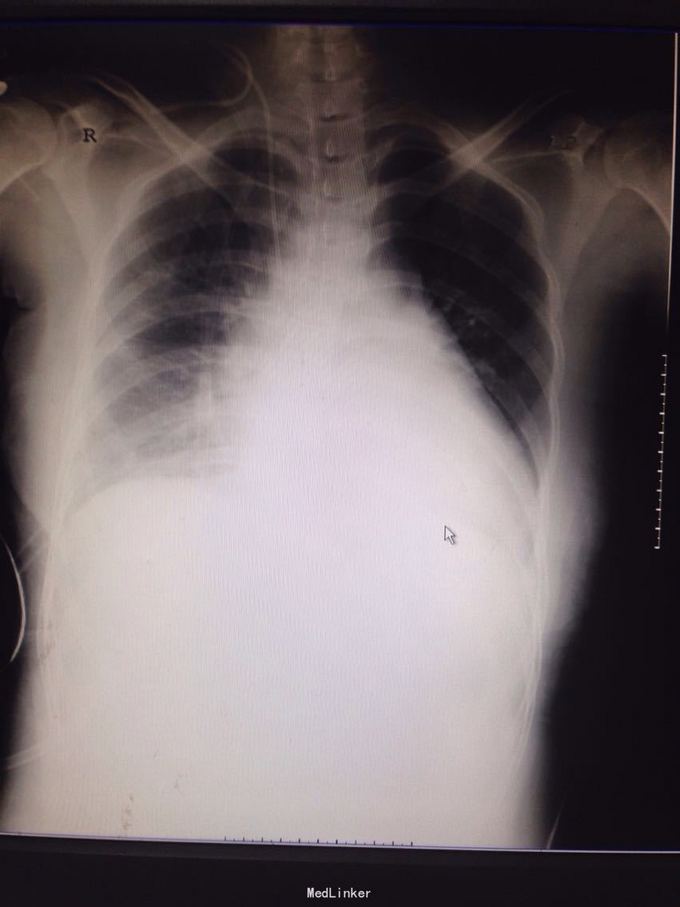

主诉:间歇性胸痛2年 病史:患者2年前无明显诱因出现胸痛,呈间歇性隐痛,约1至3月出现胸痛一次,每次持续约3-5天,近半年来感胸痛较前频发。并出现发作时胸闷、气促。至当地医院就诊,作胸部CT提示纵隔占位性病变。遂入我科手术治疗。

查体:双眼眼睑无明显下垂,结膜无充血,巩膜无黄染。双瞳孔等大等圆。气管居中,双侧胸廓无明显畸形,呼吸运动无受限。右侧中胸部叩诊浊音,左侧胸部叩诊清音,双肺呼吸音清,无啰音。 胸部CT提示右纵隔肿瘤。

诊断:右纵隔占位:畸胎瘤可能性大 处理:右侧前外侧切口第四肋进胸完成肿瘤切除,术中切开肿瘤见大量毛发形成,未见骨骼及牙齿形成

术后三天拔除胸腔引流管,七天出院,出院后一月随诊右侧胸腔无异常 讨论:前纵隔肿瘤年轻患者以畸胎瘤较常见,手术切除一般效果较好,以良性肿瘤居多。